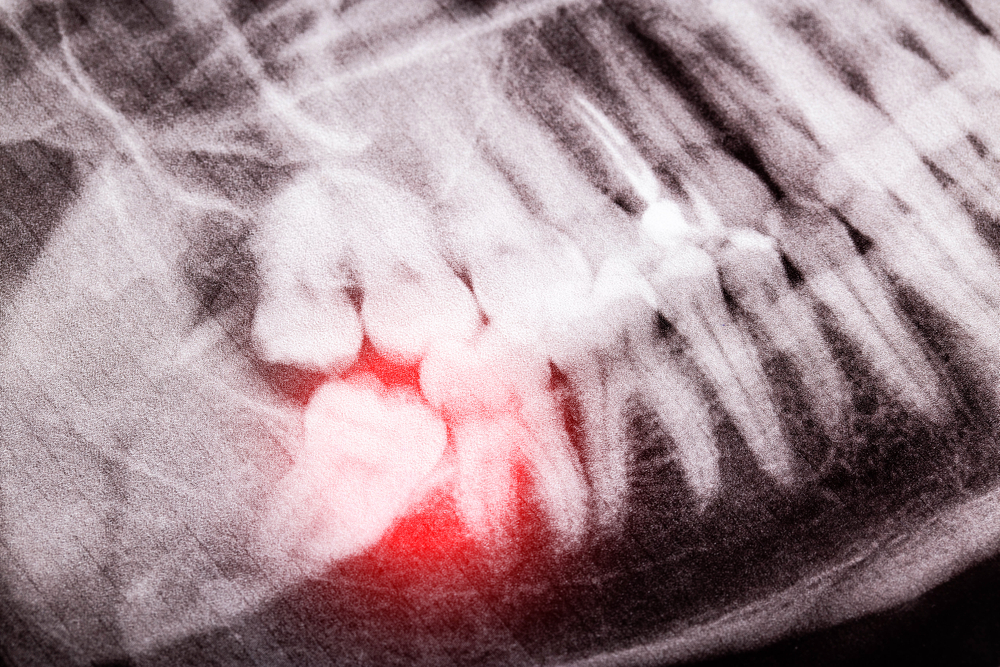

Infected Tooth Dentist in Vista

An infected tooth requires emergency care. If you notice the signs of an infected tooth and find an experienced dentist in time, it is possible to save the tooth and restore your oral health. If you are searching for an “infected tooth dentist near me”, then you probably understand the importance of receiving proper treatment …

Tooth Abscess Treatment in Vista CA

An abscessed or infected tooth is a dental problem caused by bacteria penetrating through your tooth enamel and dentin to reach the pulp (pulpitis), such that pus begins to collect within. It can also occur when bacteria gets trapped in deep gum pockets. This results in a number of unpleasant symptoms, including: Types of tooth …